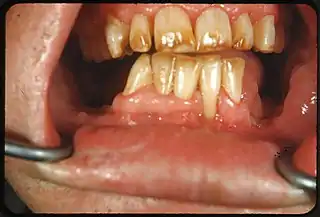

![]() Manchas de color blanco o café en la superficie dental | ||

Cuadro clínico

Dependiendo del nivel de fluoruro en el agua, el aspecto de los dientes moteados, puede variar:

- Cambios caracterizados por manchas de color blanco en el esmalte,

- Cambios moderados manifestados por áreas opacas blancas que afectan más el área de la superficie dental.

- Cambios moderado e intensos que muestran formación de fosetas y coloración parda de la superficie e incluso:

- Apariencia corroída.

Los dientes afectados moderada o intensamente pueden mostrar tendencia a desgastar, e incluso fracturar, el esmalte. Algunos estudios demuestran que estos dientes presentan dificultades para sostener las restauraciones dentales.